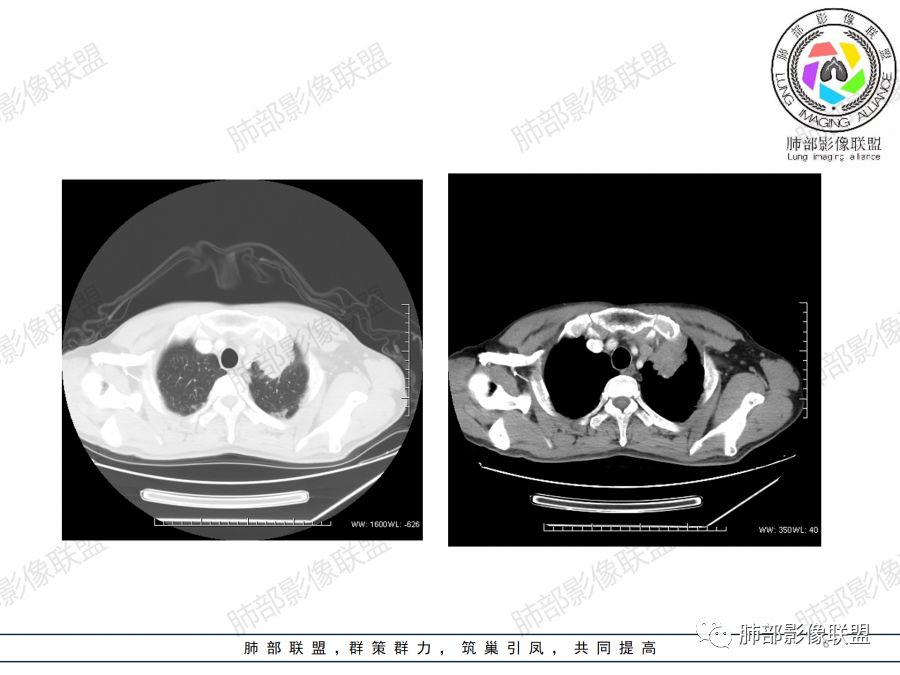

男,47岁,咳嗽咳痰一月。病灶位于左内乳动脉内缘,定位肺内,呈团片状异常密度影,整体沿支气管气管束走形分布,由肺门达胸膜下,于近肺门侧病灶形态相对较小,病灶远端相对较大,病灶整体密度偏均匀,强化偏明显,病灶内见多发支气管扩张并粘液栓形成,且扩张支气管粗细不均,直达病灶以远,病灶内血管走形正常、粗细均匀,病灶周围见边缘模糊磨玻璃及少许腺泡结节。左肺门及纵隔略大淋巴结,左侧胸膜局限性增厚。诊断:左肺上叶前段异常密度影,炎性肉芽肿性病变可能,结核不能除外,建议穿刺活检除外恶性肿瘤。

2.双上肺多发病灶,左肺上叶病灶沿血管支气管束分布,由外朝内,以平直收缩为主,周围有斑片渗出,胸膜糊墙,支持炎性病灶或是伴有肿瘤灶可能性。

3.病灶内多支支气管粘液栓,炎性及恶性均可,但是炎性多于恶性;强化杂乱不均,病灶内小灶坏死比规则,支持炎性肉芽肿病变。

鳞癌病灶如较大,强化常不够显著且多见相对大范围湖泊样坏死。

4. 应仔细观察病变的支气管情况,如果支气管出现腔内结节或阻塞征象,需要提示临床干预,用支气管镜、穿刺等手段来进一步确诊。